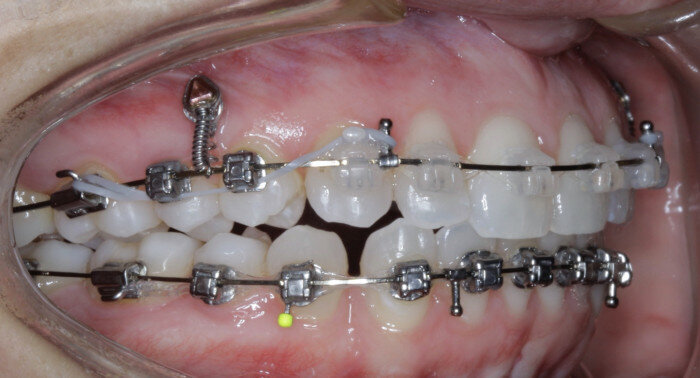

TADs are placed at the second visit with a 14 × 25 mm copper (Cu) and nickel–titanium (NiTi) wire and are tied from the anchor to the wire with an elastic thread (surgical thread; Fig. 6). Once the patient has progressed to larger Cu–NiTi wires and stainless steel, the TADs are tied to the wire using a power chain looped to the wire, or NiTi closing springs, depending on the thickness of the tissue (Figs. 7 & 8).

Once the intrusion has been completed, the TADs are tied to the wire and vertical elastics are used to close the bite without relapse of the intrusion. If buccal crown tip is seen, owing to the movement created by the intrusion, a power chain torquing sling is used to encourage lingual crown tipping and to prevent flaring of the incisors (Fig. 9). Once the case has been completed, the appliance is removed and a gingivectomy is performed to idealise the tissue shape and the final contours are made to the hard tissue (Figs. 10–12, end of treatment).